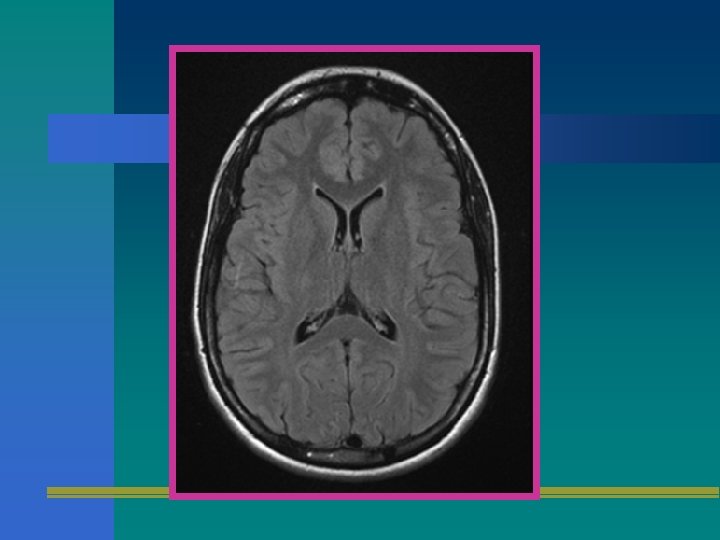

FLAIR • FLUID ATTENUATED INVERSION RECOVERY • ESTA SECUENCIA ANULA LA SEÑAL PROVENIENTE DE FLUIDOS. • ANULA EL LCR LO QUE MEJORA EL CONTRASTE EN LESIONES PERIVENTRICULARES.